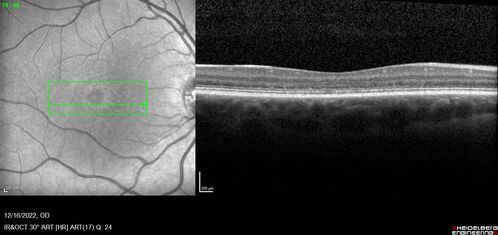

Stargardt Disease - Very Mild - 24 year old

This patient has 3 different ABCA4 mutations. His mother and sister have stargardts and his father has RP. His sisters images are also on Retinagallery.com